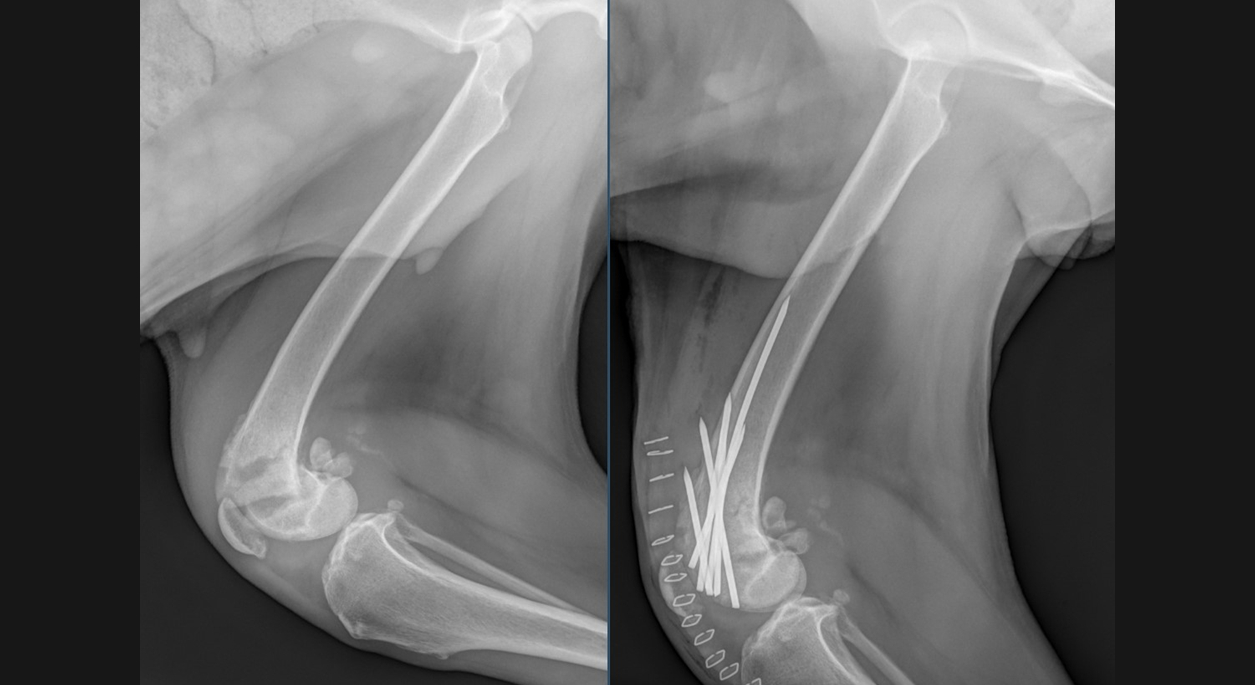

The right femoral trochlear fracture was approached and found to be moderately unstable. The fracture extended medial to lateral through the proximal femoral trochlea, resulting in articular involvement both above and below the fracture line. After severing fibrous adhesions between the bone fragments, the fracture could be reduced with significant effort. The fracture was ultimately stabilized with six IM pins placed in cross-pin fashion. Postoperative fracture reduction and alignment were considered good. The left FHNO was routine. Sophie is now on the road to recovery and will hopefully regain good function of both pelvic limbs.